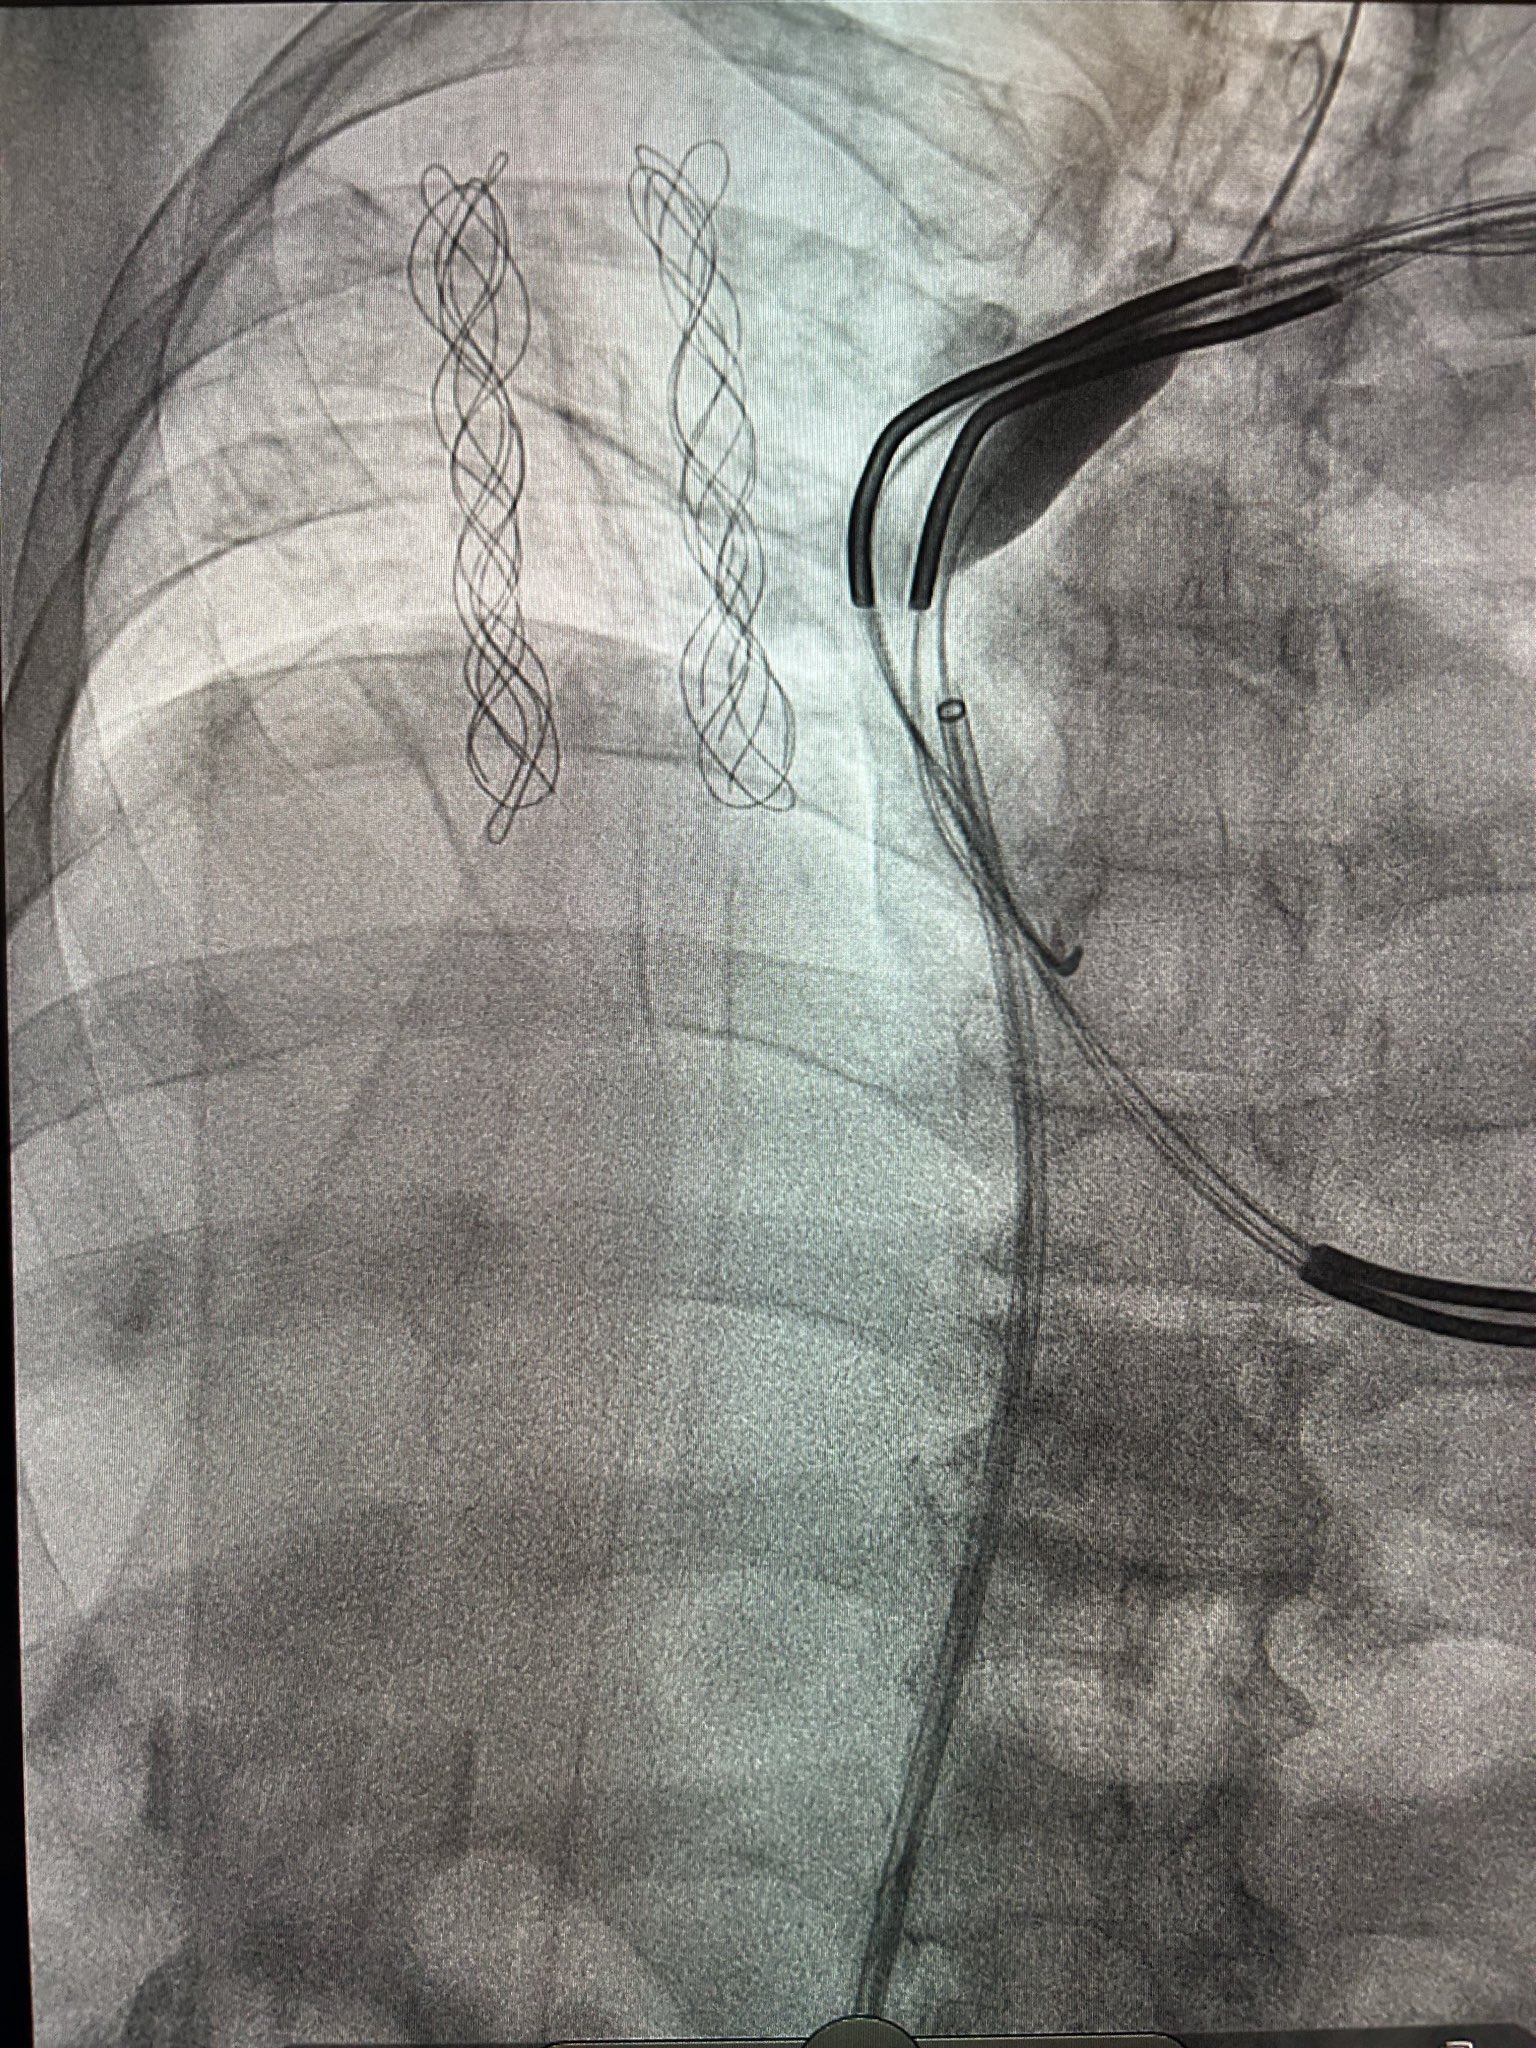

Patient with an abandoned 16 year old dual coil ICD lead, RA lead fracture, and generator at ERI.

Shockwave with a 12mm balloon to the axillary, subclavian, and SVC.

Extracted both leads with 16Fr laser and preserved existing ICD lead.

#Epeeps #extraction #shockwave